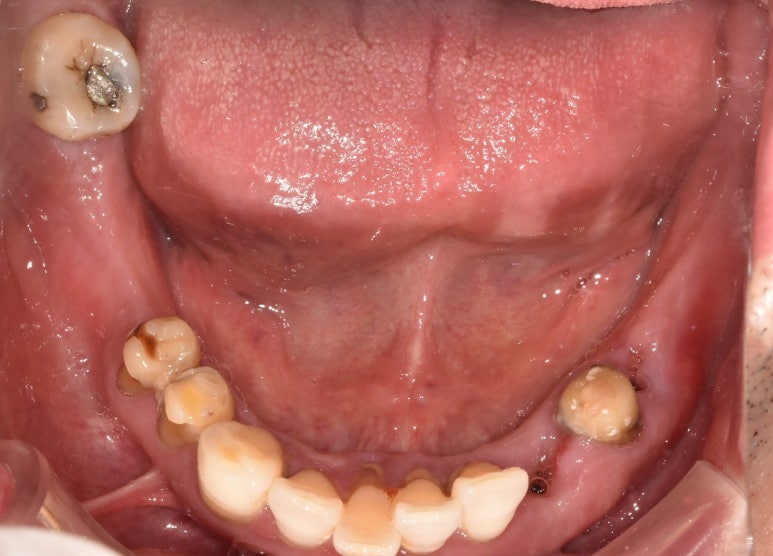

임플란트건강보험 시술 전후 모습

(전) 2021-11-05 (후) 2022-08-26

실제 사진을 보니 확실히 얼마나 달라졌는지 느낌이 오시죠? ^^

치아를 상실했던 부분이 완전히 채워진 것은 물론, 기존에 약했던 치아들도 모두 튼튼하게 교체해

음식을 씹을 때 전혀 지장이 없으시게끔 치료가 완료되었습니다.

환자분께서도 씹는 즐거움을 다시 느끼게 되셨다며 너무 좋아하셨던 모습이 눈에 선합니다 ^^